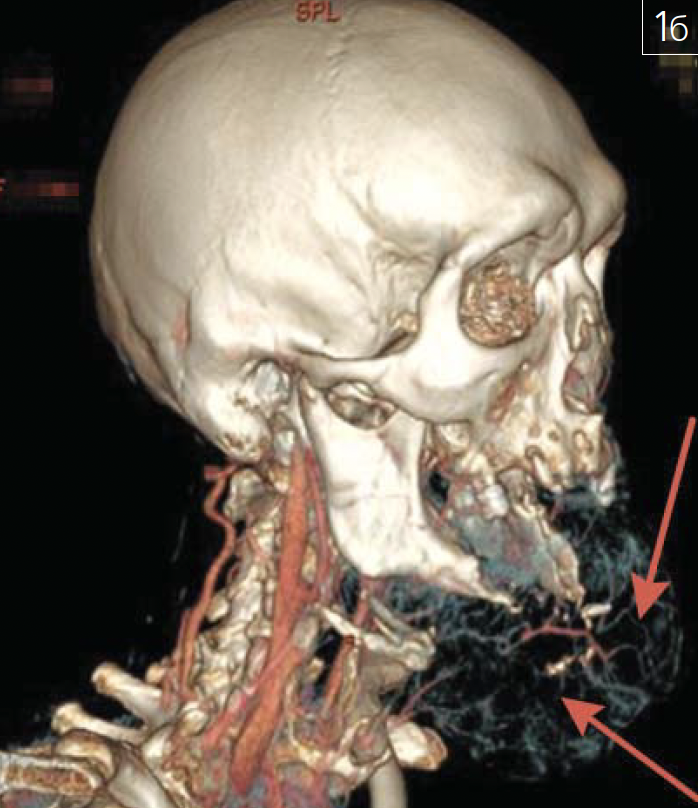

Особое место в практике врача-стоматолога, челюстно-лицевого хирурга и рентгенолога занимают ятрогении (рис. 13 а-в; 14 а, б; 15 а-в; 16; 17).

Рис. 16. Зуб 2.7, являющийся опорой мостовидного протеза, располагается в карциноме верхнейчелюсти слева (зона интереса указана на рисунках красными стрелками): а – МСКТ черепа, плоскостнаяреконструкция в корональной плоскости; б – МСКТ черепа, плоскостная реконструкция в атипичнойсагиттальной плоскости